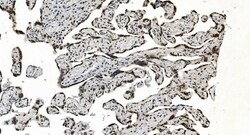

Adding 0.2 mL of distilled water will yield a concentration of 500 μg/mL. Positive Control - WB: human Jurkat whole cell, human PC-3 whole cell, human Raji whole cell, human K562 whole cell, human Caco-2 whole cell, human MCF-7 whole cell, human HL-60 whole cell, human PC-3 whole cell. IHC: human breast cancer tissue, human gastric cancer lymph node tissue, human liver cancer tissue, human ovarian serous adenocarcinoma tissue, human pancreatic cancer tissue, human placenta tissue, human rectal cancer tissue. ICC/IF: MCF-7 cell. Flow: K562 cell. Store at -20°C for one year from date of receipt. After reconstitution, at 4°C for one month. It can also be aliquotted and stored frozen at -20°C for six months. Avoid repeated freeze-thaw cycles.

| Applications | ELISA, Flow Cytometry, Immunohistochemistry (Paraffin), Western Blot, Immunocytochemistry |